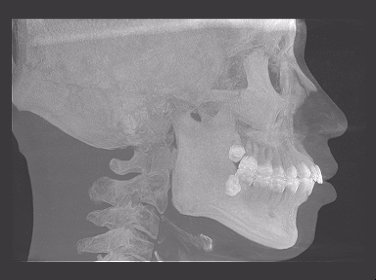

术前头颅侧位片

- 矢状向:安氏I类双颌前突,上下切牙唇倾

- 垂直向:深覆合I度,下颌Spee曲线深

- 横向:牙弓狭窄

- 中线:上中线对正

- 拥挤度:轻度